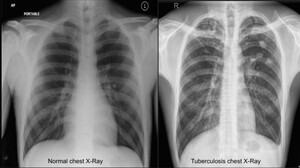

An automated tuberculosis detection approach using deep learning and machine learning techniques from chest X-ray images: a step towards effective diagnosis

Abu Saleh Mohammad Nabil, Md. Musfiqur Rahman Mridha, Md. Shahid Ahammed Shakil, Iffath Tanjim Moon, Md. Fayzul Islam, Md. Jamil Chaudhary, Sakib Imtiaz, Md. Taufiq Khan

Pol J Radiol, 2026; 91(1): 46-55